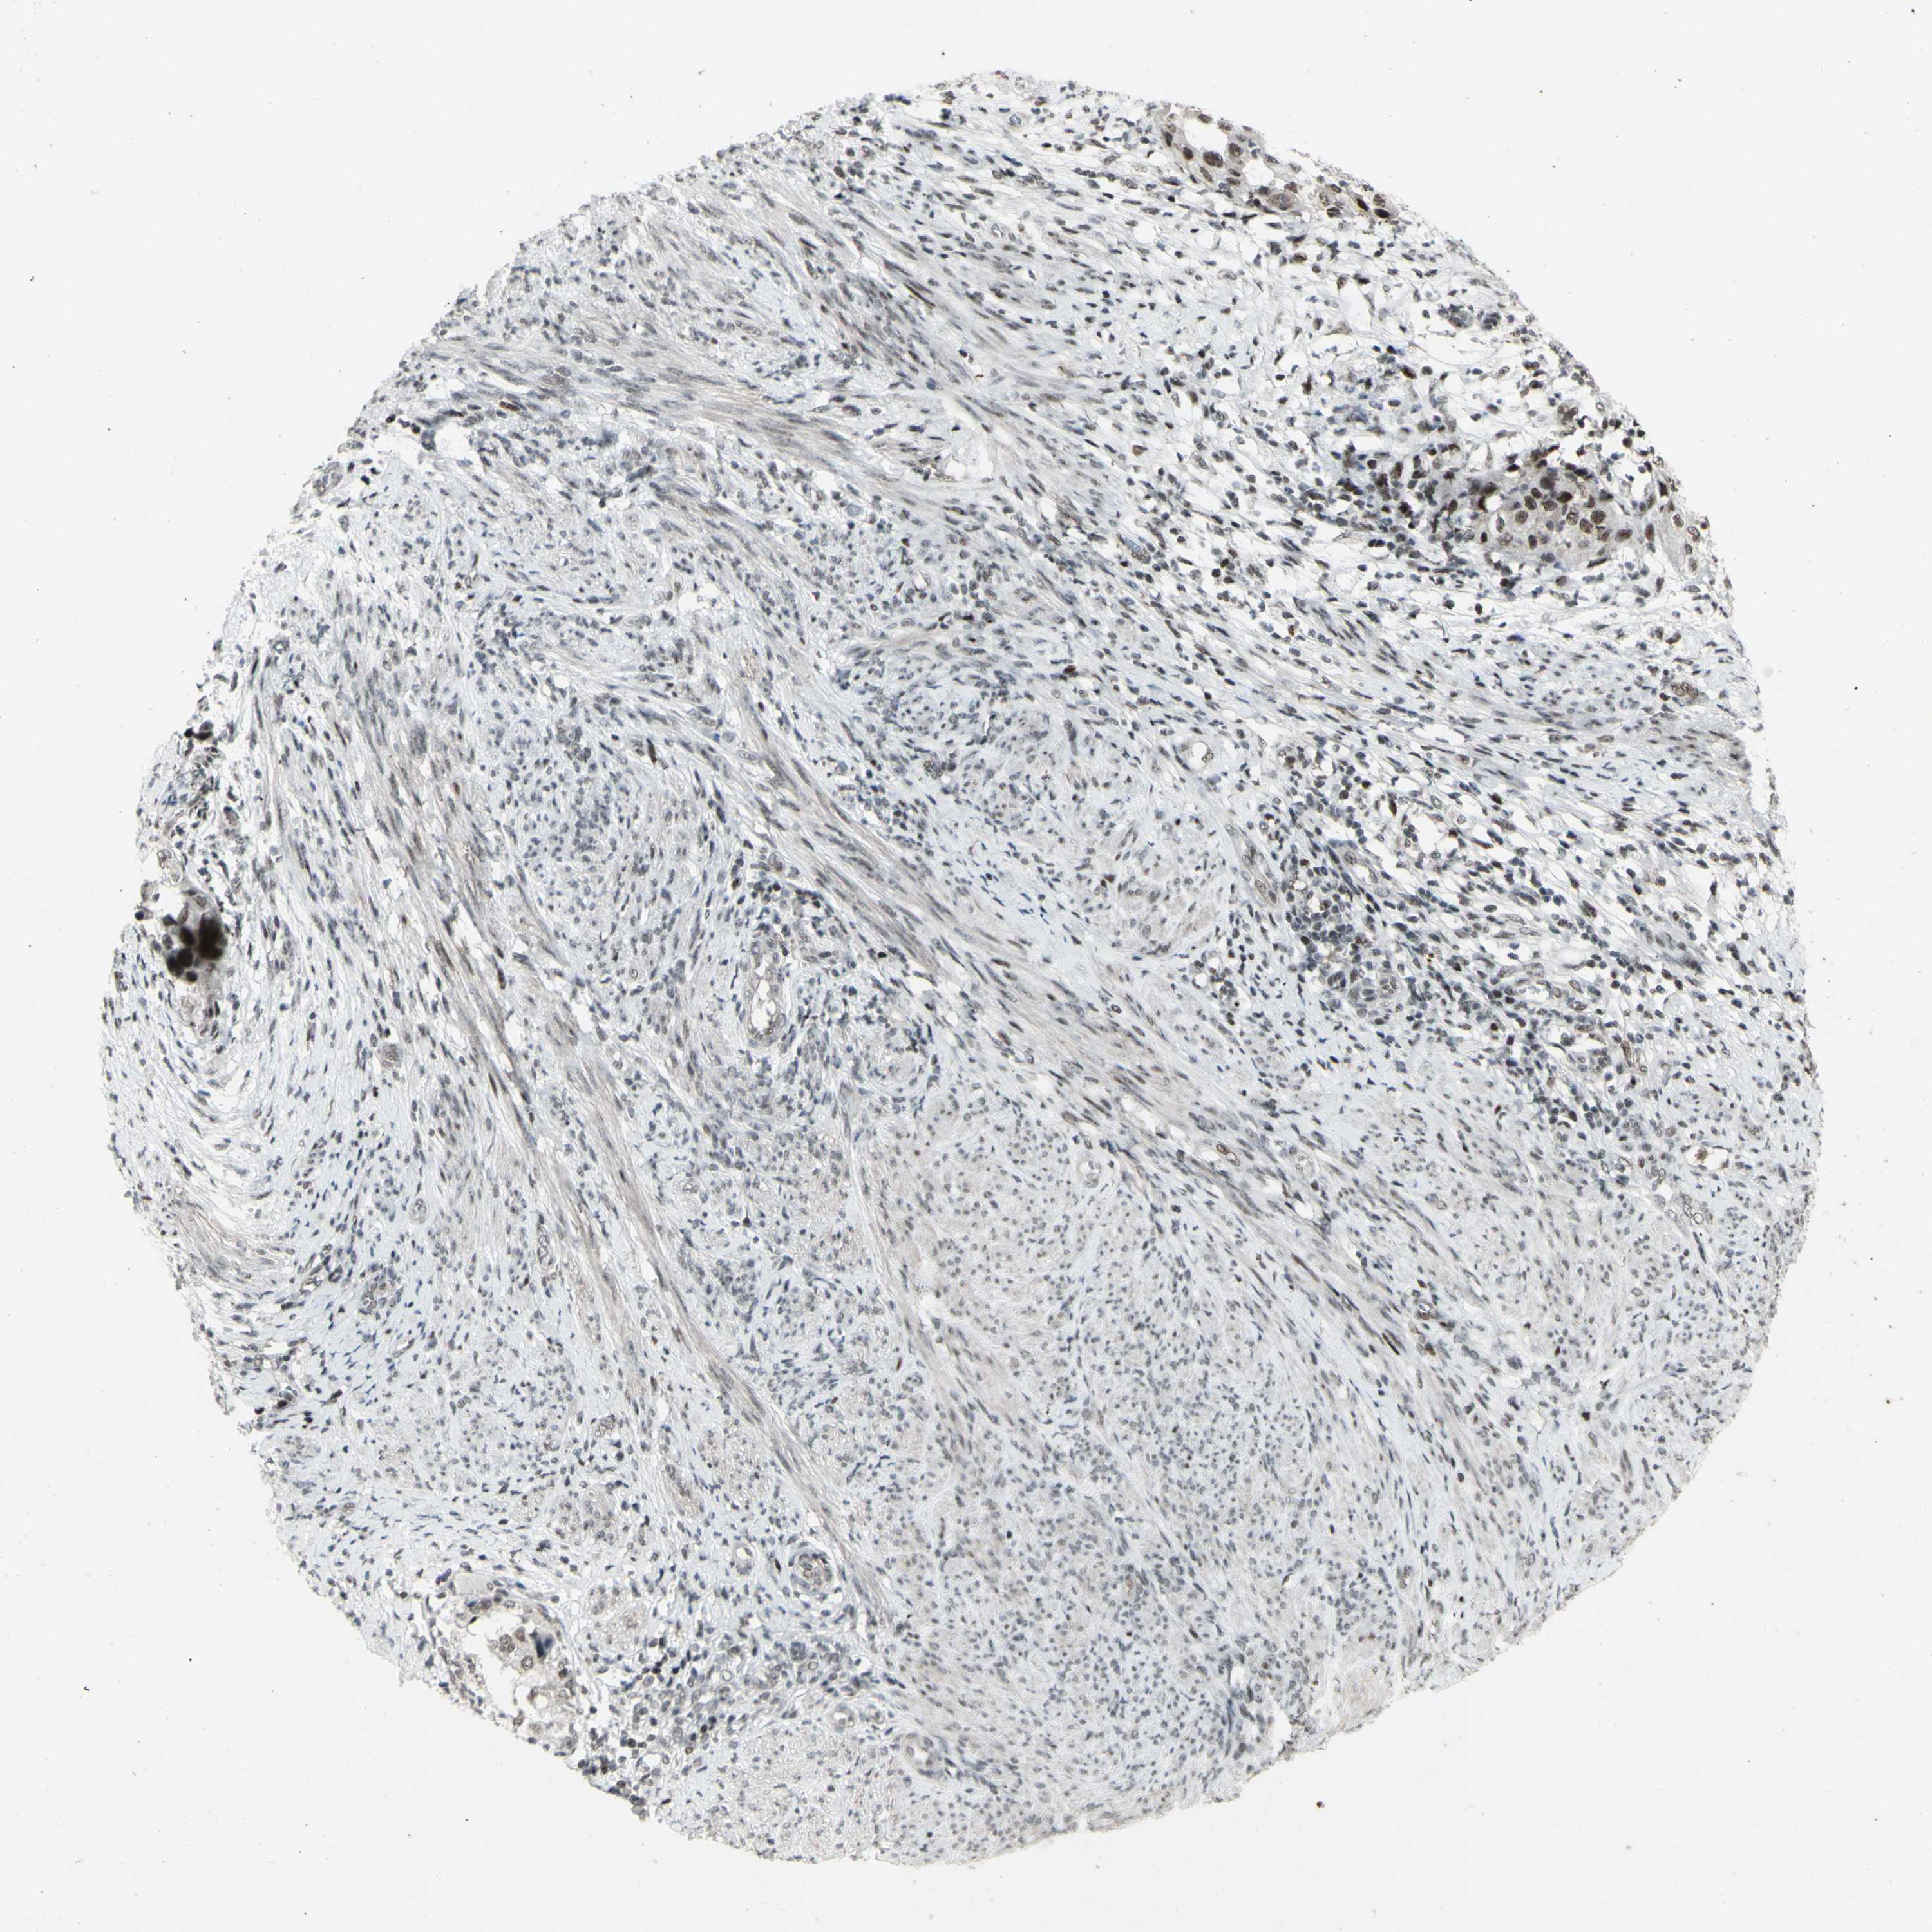

ENDOMETRIAL CANCER - Protein expressioni

A mouse-over function shows sample information and annotation data. Click on an image to view it in a full screen mode. Samples can be filtered based on level of antibody staining by selecting one or several of the following categories: high, medium, low and not detected. The assay and annotation is described here.

Note that samples used for immunohistochemistry by the Human Protein Atlas do not correspond to samples in the TCGA dataset.

Antibody stainingi

Antibody staining in the annotated cell types in the current human tissue is reported as not detected, low, medium, or high, based on conventional immunohistochemistry profiling in selected tissues. This score is based on the combination of the staining intensity and fraction of stained cells.

Each image is clickable and will lead to virtual microscopy that enables deeper exploration of all samples and also displays staining intensity scores, fraction scores and subcellular localization as well as patient and tissue information for each sample.

Antibody HPA036382

Antibody CAB012416

Staining

High

Medium

Low

Not detected

Intensity

Strong

Moderate

Weak

Negative

Quantity

>75%

75%-25%

<25%

None

Location

Nuclear

Cytoplasmic/membranous

Cytoplasmic/membranous,nuclear

Adenocarcinoma, NOS